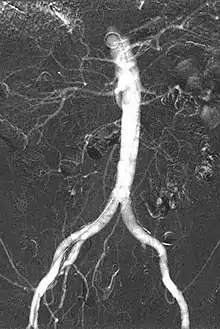

Carbon dioxide angiography is a diagnostic radiographic technique in which a carbon dioxide (CO2) based contrast medium is used - unlike traditional angiography where the contrast medium normally used is iodine based – to see and study the body vessels.[1] Since CO2 is a non-radio-opaque contrast medium, angiographic procedures need to be performed in digital subtraction angiography (DSA).

Carbon dioxide is a negative contrast medium and it has a low radiopacity (while iodinated contrast media are defined as positive contrast media due to their high radiopacity). Contrast is caused by the different X-ray absorption coefficients between the tissue and the contrast agent. In the vascular imaging results produced using CO2, vessels look brighter rather than the surrounding tissues, because the contrast medium absorbs less X-ray radiations rather an iodine-based contrast medium, where the vessel are displayed in black.

The CO2 does not mix with blood. At atmospheric pressure CO2 is in gaseous form and, when it comes out from the catheter, it forms a train of bubbles which displaces blood, causing a transient ischemia, in relation to the bloodstream (systolic pressure). When added together by DSA “stacking” software,[5] the result is a composite diagnostic image of the frames.